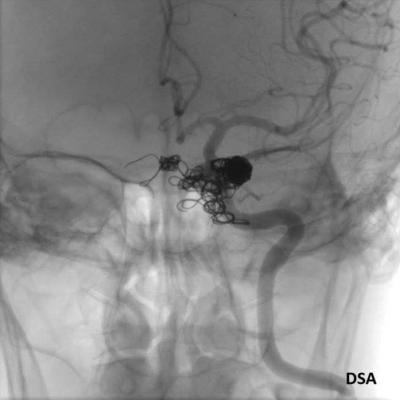

- C) DSA incelemelerinde sol eksternal karotid arter (ok) kateterizasyonunda kontrast maddenin kavernöz sinüse (ok) geçtiği izleniyor. Tedavi sonrası görüntüde kavernöz sinüs ile karotis arteriyel sistem arasında bulunan fistül traktına coil embolizasyon (ok) işlemi uygulandığı görülüyor.

- DSA: Fistülün akış hızını karakterize ederek direkt ve indirekt fistülleri net olarak ayırabilir. ICA defektinin tam anatomik yerini ve ICA veya ECA dural besleyicilerini gösterir. Ayrıca DSA ile endovasküler tedaviler yapılabilmektedir.

- Olgumuzun DSA incelemelerinde sol ICA ve ECA’dan kavernöz sinüse fistülöz bağlantı olduğu izlenmiş ve coil embolizasyon işlemi uygulanarak tedavi edilmiştir.